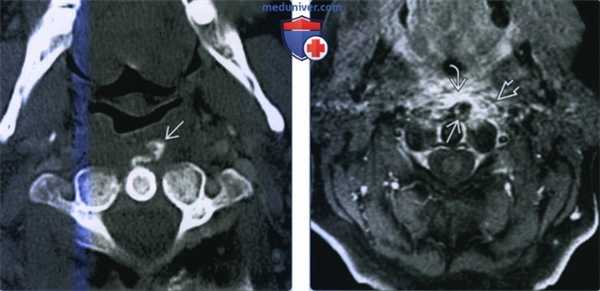

(Слева) КТ с КУ, аксиальный срез: признаки кальцификации сухожилия длинной мышцы шеи на уровне С1. Отмечается отек окружающих мягких тканей.

(Справа) Т1-ВИ с КУ, сагиттальная проекция: контрастное усиление сигнала утолщенных превертебральных мягких тканей, свидетельствующее о наличии здесь воспаления. Фокус кальцификации определяется в виде низкоинтенсивного очага. Наблюдаемые воспалительные изменения полностью разрешились в течение одной недели без назначения какой-либо терапии или хирургического вмешательства. (Слева) Т1-ВИ, FS c КУ, аксиальная проекция: контрастное усиление сигнала превертебральных мягких тканей, соответствующее воспалительным изменениям. Фокус кальцификации определяется в виде очага низкой интенсивности сигнала.

(Слева) КТ с КУ, фронтальный срез: кальцификация превертебральных тканей Тендинит длинной мышцы шеи обычно проявляется на КТ появлением пирамидальных депозитов кристаллов гидроксиапатита кальция кпереди от С1 и С2 позвонков. Однако, данные недавних исследований свидетельствуют о возможности появления изменений также на уровнях С4-С5 и С5-С6.

(Справа) КТ с КУ, аксиальный срез: утолщение превертебральных мышц. Круг заболеваний для дифференциальной диагностики с тендинитом длинной мышцы шеи включает заглоточный абсцесс, инфекционный спондилит, травмы и аспирацию инородного тела. (Слева) КТ с КУ, фронтальный срез: скопление жидкости в заглоточном пространстве, оттесняющее длинные мышцы шеи кзади Скопление жидкости при тендините длинных мышц шеи не накапливает контраст и имеет удлиненную форму. Это отличает его от округлого контрастирующегося по периферии жидкостного скопления при заглоточном абсцессе.